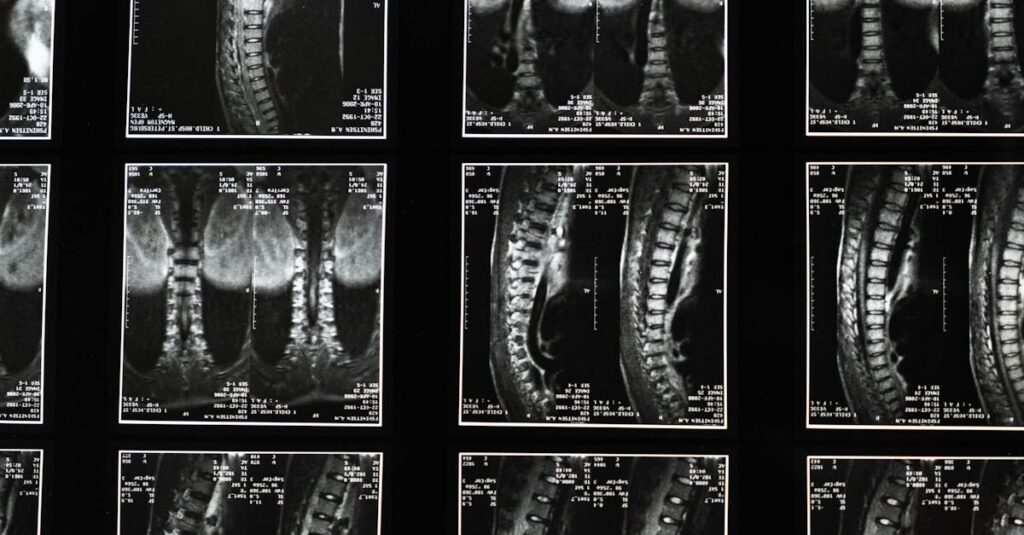

Quels examens sont nécessaires avant de commencer un traitement de décompression pour la sciatique?

Une IRM ou une radiographie est généralement recommandée pour évaluer l’état de la colonne vertébrale.